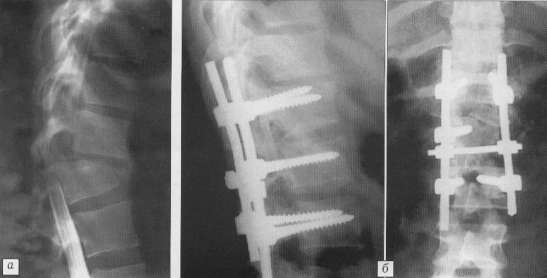

и пластиной "Оrion" (рис. 2). При вправлении позвонков использовался

Рис. 2. Больной 49 лет: а

- переломовывих С5 позвонка; б - проведено двухэтапное оперативное лечение:

резекция суставных отростков на уровне С5-6 и затeм открытое вправление

позвонка пластиной "Оrion" в сочетании с передним спондилодезом

трансплантатом из крыла подвздошной кости. |